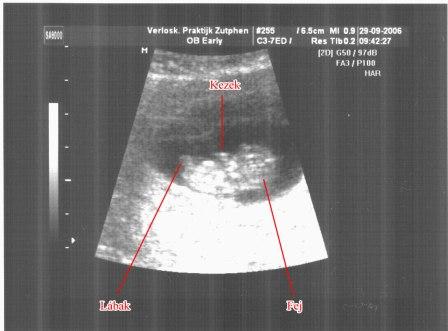

tegnap meg volt az elsö ultrahangunk. Azt hittem nem fogunk semmit látni, de ahhoz képest,,,,,,, egy iszonyatosan kis izgága, hiperaktív pocaklakóm van. :lol: :lol:

Egy másodpercre nem állt le a lábainak és kezeinek mozgatásával.

Valami csoda volt.

Itt van a pocaklakóm elsö ultrahangja: